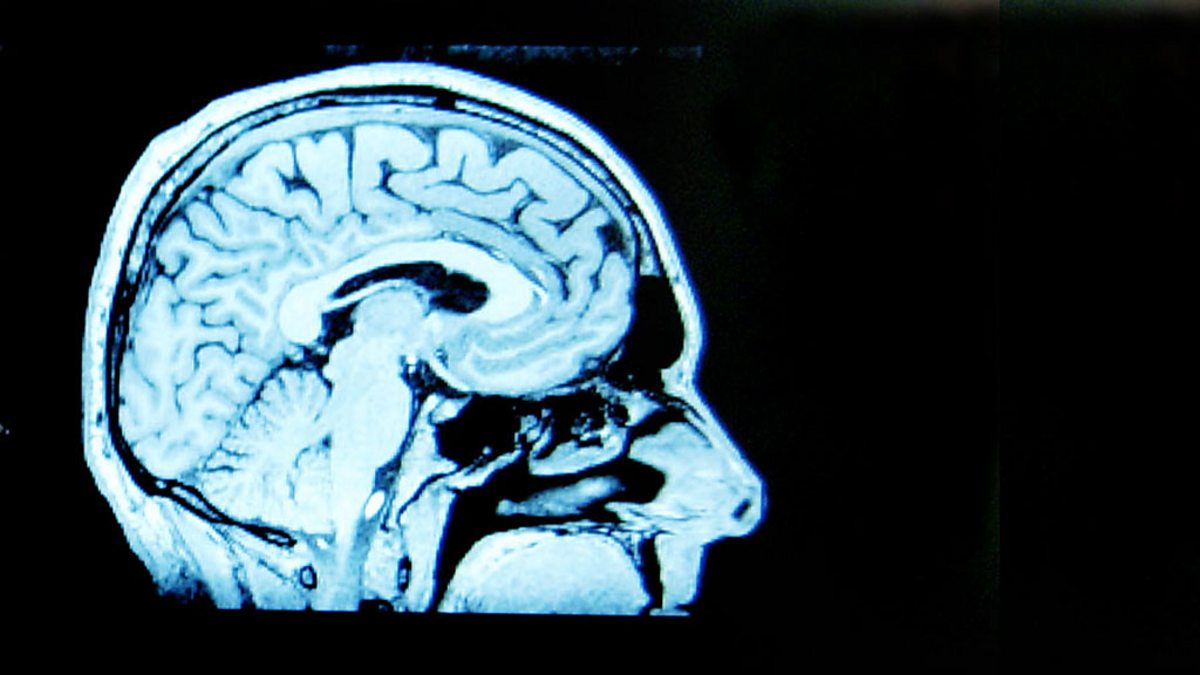

Changing Minds

A short season of programmes looking at the issue of mental health, including historic attitudes, current research and the varied experiences of the people affected.